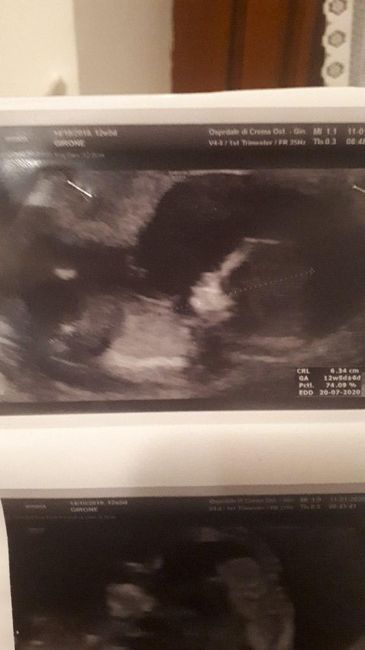

Esperte metodo ramzi e nub theory a me!!π

Ciao a tutte!πSo che questi metodi non hanno nessuna valenza scientifica.. ma come si suol dire: la curiositΓ Γ¨ donna!πVi allego due mie ecografie, entrambe esterne.....